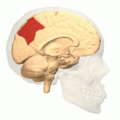

Precuneus of left cerebral hemisphere (shown in red).